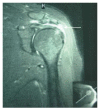

Figures